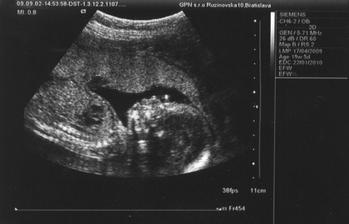

Naše krásne dievčatko